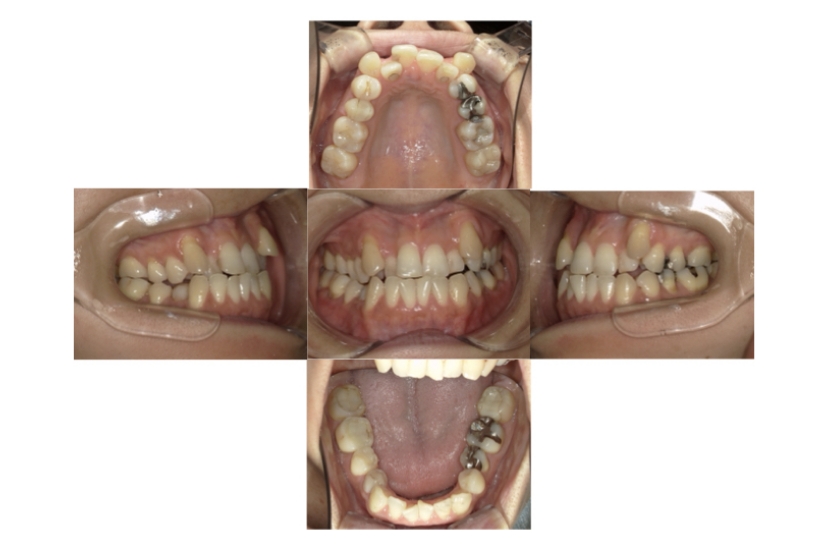

症例1

上顎前突、叢生

抜歯

ブラケット矯正

上下顎叢生、上顎前突(出っ歯、上下の前歯のガタガタ)のケースです。

装置はラビアル(上下表側)で、上顎の小臼歯を2本抜歯を行っています。抜歯したスペースを使って、上の前歯の後方移動と叢生(ガタガタ)と出っ歯の改善を行っています。下は歯と歯の間にIPR(隣接面削合)を行い、スペースを確保し、叢生の改善を行っています。

主訴 前歯のガタガタと出っ歯が気になる。

年齢・性別 47歳 女性

お住まいの地域 神奈川県川崎市

治療方針 抜歯スペースおよびIPRを利用して上前歯の叢生(ガタガタ)の改善

抜歯部位 上顎左右第一小臼歯

使用装置 ラビアル(上下表側)、顎間ゴム

治療期間 2年0か月

治療回数 15回

リテーナー クリアリテーナー

BEFORE

AFTER